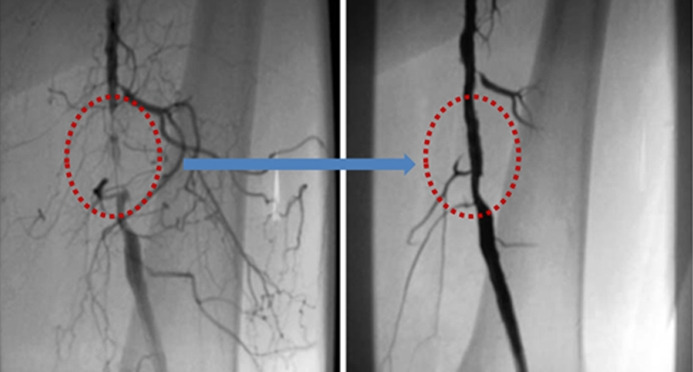

6_1.jpg (왼쪽)좁아진 대퇴동맥에 풍선확장술 시행, (오른쪽)시행 후 정상적인 혈류 흐름을 보인다.

말초동맥질환은 혈관이 많이 막히지 않은 초기에 발견하면 항혈소판제, 혈관확장제 등 약물치료와 콜레스테롤 관리를 위한 식습관, 생활습관 개선으로 나아질 수 있습니다.

시술은 국소 마취 후 풍선 확장술(혈관에 풍선을 넣고 풍선을 부풀려 혈관을 넓혀주는 시술)이나 스텐트 삽입술(혈관에 그물망 스텐트를 삽입해 좁아지는 것을 방지하는 시술)을 시행합니다. 최근에는 죽종절제술(혈관 내벽을 깎아 넓히는 시술) 시행 빈도가 증가하고 있습니다.